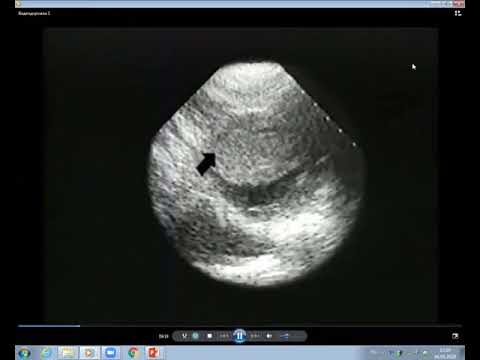

Видеолекция клиники Мэйо Кардиомиопатии 7 я лекция